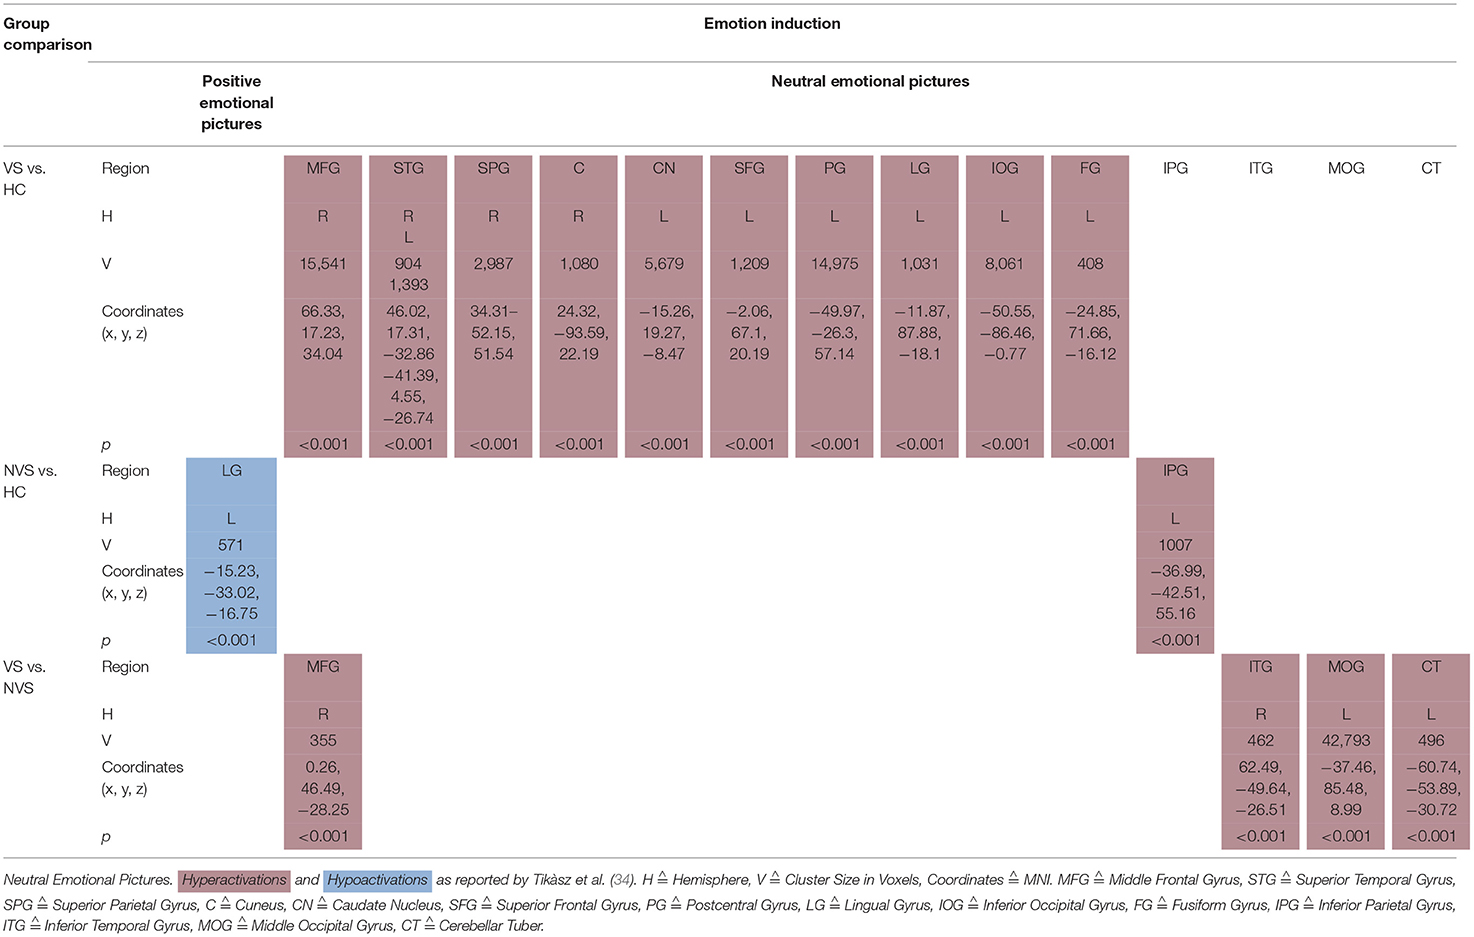

Tikàsz et al. (34) showed also positive and neutral emotional pictures to their participants (see Table 5C).

When viewing positive pictures, NVS vs. HC hypoactivated the left lingual gyrus.

VS vs. HC showed significant hyperactivations in response to neutral pictures in right middle frontal gyrus, right superior temporal gyrus, right superior parietal gyrus, right cuneus, left caudate nucleus, left superior frontal gyrus, left postcentral gyrus, left lingual gyrus, left inferior occipital gyrus, and left fusiform gyrus. NVS vs. HC hyperactivated the left inferior parietal gyrus.VS vs. NVS, when viewing neutral pictures, hyperactivated right middle frontal gyrus, right inferior temporal gyrus, left middle occipital gyrus, and left cerebellar tuber.

Positive and Neutral Emotional Pictures

Previous literature concerning healthy persons has shown that visual stimuli generally activate the occipital cortex and the amygdala (61). Furthermore, the medial prefrontal cortex was found to play a role in emotional processing across all categories independently of the emotion. Literature on neutral image processing in schizophrenia is sparse.

Non-violent persons with schizophrenia showed significantly lower activation in the left lingual gyrus than HC when viewing positive pictures.

In the neutral emotional pictures condition, violent persons with schizophrenia compared with HC showed significant hyperactivations in right middle frontal gyrus, right superior temporal gyrus, right superior parietal gyrus, right cuneus, left caudate nucleus, left superior frontal gyrus, left postcentral gyrus, left lingual gyrus, left inferior occipital gyrus, and left fusiform gyrus (34).

Non-violent persons with schizophrenia as opposed to HC showed significant hyperactivation in left inferior parietal gyrus (34). This finding fits into a previous study where Habel et al. (69) showed that persons with schizophrenia elicited hyperactivations in the frontal and cingulate areas and the basal ganglia.

Violent vs. non-violent persons with schizophrenia showed, when viewing neutral pictures, hyperactivations in the right middle frontal gyrus, right inferior temporal gyrus, left middle occipital gyrus, and left cerebellar tuber (34). The authors discuss that it remains unclear how these activation patterns are related to aggressive behavior.